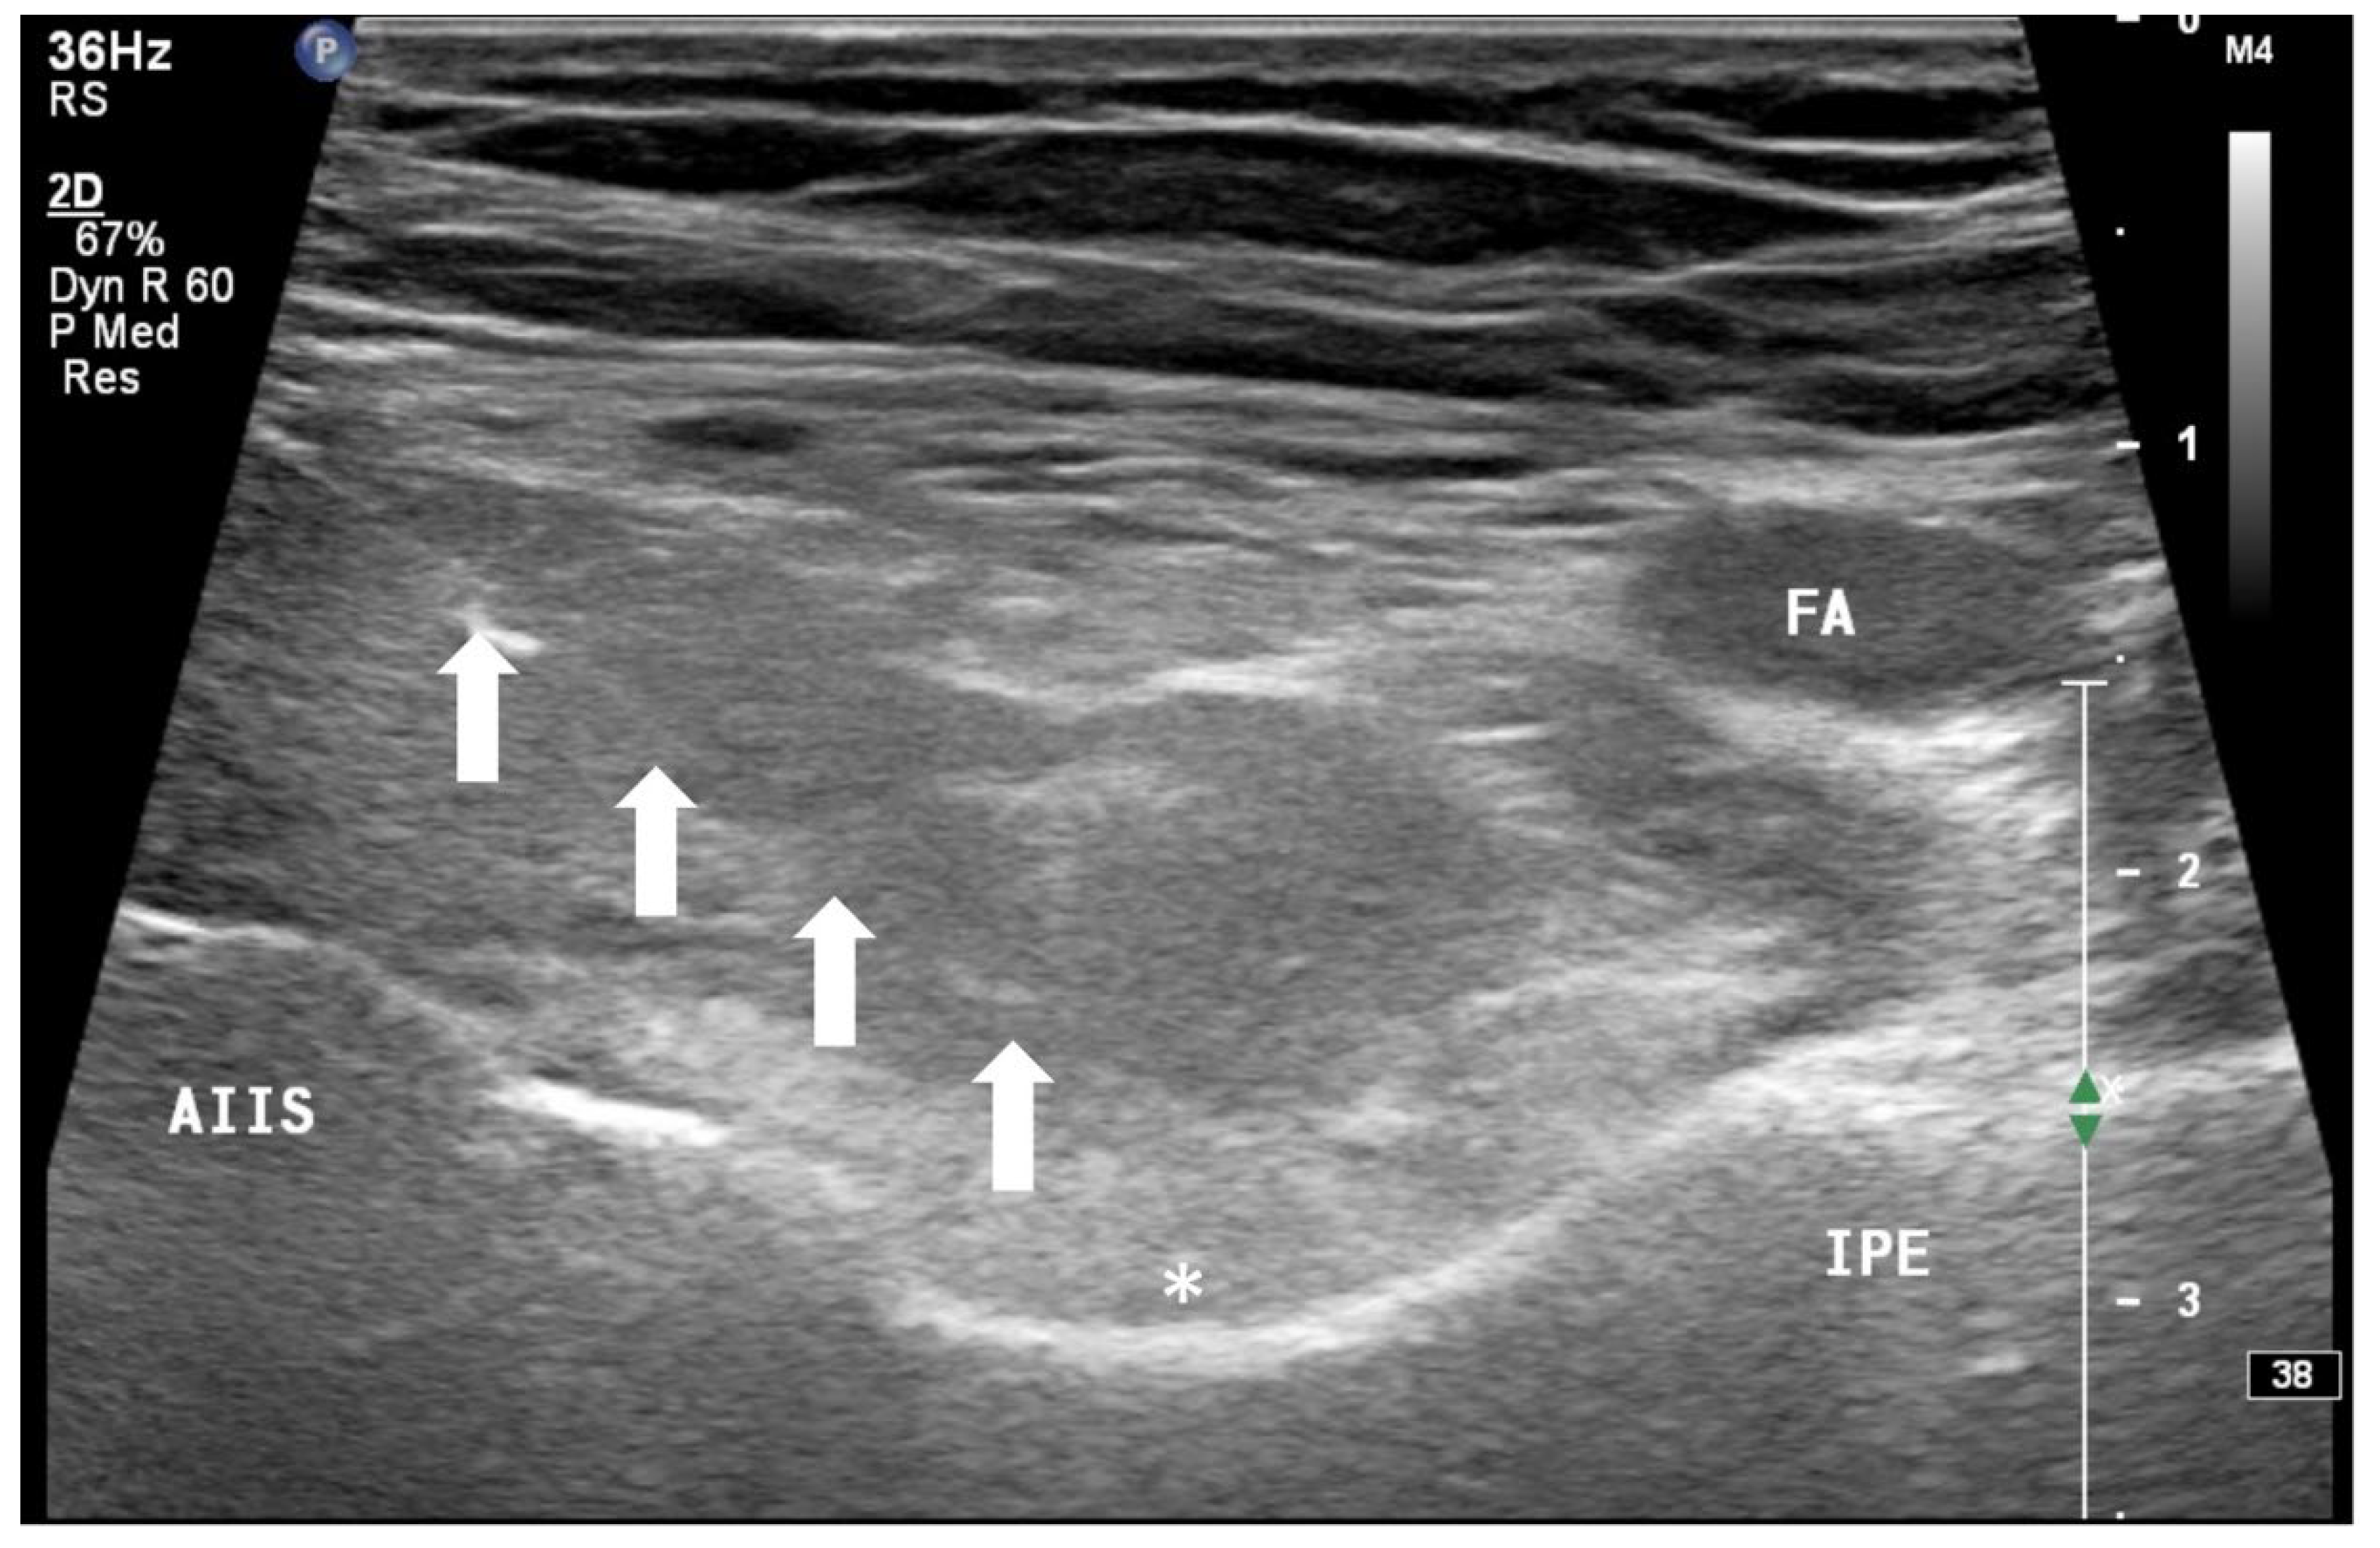

In addition to the classical PENG injection, our modified approach highlighted the addition of pericapsular infiltration in the iliopsoas plane to cover the low articular branch of the femoral nerve and a sagittal approach to target the ONAB. The algorithm was still used to perform diagnostic blocks, followed by alcohol neurolysis 10 min later for those with a positive diagnostic block in the same setting under real-time ultrasound guidance (Philips Affiniti 70, 5–12 MHz linear probe or 1–5 Hz curved probe depending on the depth of the target). In the modified approach, the procedure consisted of 3 needle insertions with the use of 22-gauge 10 cm Quincke needles. The first needle for the high femoral nerve articular branches (high FNAB branches) and AON was inserted in the same way as the PENG approach between the anterior inferior iliac spine (AIIS) and the iliopubic eminence (IPE) deep to the psoas tendon (Figure 2 and Figure 3). A second needle for the low branches of FNAB was inserted in-plane from lateral to medial and advanced through the sartorius, rectus femoris and iliopsoas muscles. The final needle position was in the plane superficial to the iliofemoral ligament medial to the rectus femoris tendon over the femoral head (Figure 4 and Figure 5). The third injection for the obturator nerve articular branches was used to target the caudal aspect of the inferomedial acetabulum (IMA) by scanning in a sagittal plane with a caudal-to-cephalad needle trajectory. The precise localization of the caudal aspect of the IMA could be first approached via the ordinary way (an oblique scan) as described in our first case series [5]. The probe was slowly rotated obliquely until the acetabulum, femoral head, and neck were aligned in the same plane, with the superomedial acetabulum coming into view. The probe was then slid caudally with the end point being the presence of the acetabulum without the femoral head. This referred to the location of the inferomedial acetabulum. The probe was then adjusted until the IMA was in the middle of the image, followed by rotating the probe by approximately 60 degrees (Figure 6). In this scan, the pectineus, the caudal aspect of the IMA and, occasionally, the obturator externus were seen. The ONAB could be visualized in the wedge of the subpectineal space directly adjacent to the IMA. Before any needle insertion, the probe was tilted slightly medially towards the obturator foramen to look for the acetabular/posterior branch of the obturator vessels which are usually deeper than the ONAB. The needle was then inserted from caudal to cephalad in-plane until the needle tip reached the wedge space consisting of the ONAB (Figure 7). In case the wedge space could not be clearly visualized, the needle tip would then be advanced until touching the caudal bony surface of the IMA directly underneath the pectineus. Then, 0.5–1% ropivacaine (4, 3 and 2 mL, respectively) was injected into the above three landmarks. The needles were left in situ during the diagnostic test while their positions were reconfirmed by ultrasound before 100% alcohol was injected into the above targets with volumes in a 1:1 ratio between alcohol and local anaesthetics. A decrease of ≥50% in composite pain score on hip flexion at 45 degrees 10 min after the blocks signified a positive diagnostic block. As a post-neurolysis routine manner, stylets were reinserted before needle withdrawal.

Our modified approach to the ONAB would have the following advantages over the ordinary oblique approach published in our first case series [5]. First, in patients with hip fracture, their fractured limb is commonly externally rotated. This would deviate the femoral vessels to overlay the needle trajectory to the ONAB at the inferomedial acetabulum (Figure 8). This sagittal approach can reliably avoid the femoral vessels in the trajectory. Second, the sagittal scan allows us to visualize the acetabular/posterior branch of the obturator vessels underneath the ONAB, and this can minimize the chance of inadvertent puncture of these small vessels. Third, the ONAB anatomically courses along the caudal aspect of IMA instead of the lateral aspect of IMA [24]. The modified approach can potentially target the ONAB more precisely. Lastly, the modified approach allows the ONAB to be visualized clearly in non-obese patients, whereas the ordinary approach only relies on a rough bony landmark of IMA. Although a large volume of subpectineal injection may lead to a spread to the motor branch of obturator nerve [27], we did not identify any case with neurological deficit along the obturator nerve distribution in our study.

Figure 7. Approaching the ONAB in a sagittal plane from a caudal to cephalic direction. IMA: inferomedial acetabulum, P: pectineus, OE: obturator externus, *: acetabular and/or posterior branch of the obturator artery, white hollow arrow: needle.